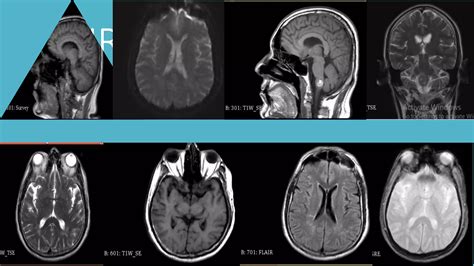

When you experience persistent, unexplained headaches, vision disturbances, or other neurological symptoms, your doctor may suggest advanced imaging to get to the bottom of the issue. One highly specialized tool used to visualize the complex network of blood vessels returning oxygen-depleted blood from the brain is Magnetic Resonance Venography (MRV). Understanding what the Magnetic Resonance Venography brain procedure entails can help alleviate anxiety and prepare you for what to expect during this diagnostic journey.

Magnetic Resonance Venography (MRV) is a sophisticated medical imaging technique that uses magnetic fields and radio waves to generate detailed images of the cerebral veins. Unlike a standard MRI, which primarily looks at the brain tissue itself, an MRV is specifically designed to assess blood flow and identify potential abnormalities within the venous system.

After the scan is complete, a neuroradiologist—a doctor who specializes in brain imaging—will analyze the images. They will look for signs of blood clots, narrowed vessels (stenosis), or malformations that could be disrupting normal circulation. Your primary physician will receive a formal report and will schedule a follow-up appointment to discuss these findings with you in detail and determine the appropriate path forward for treatment if necessary.